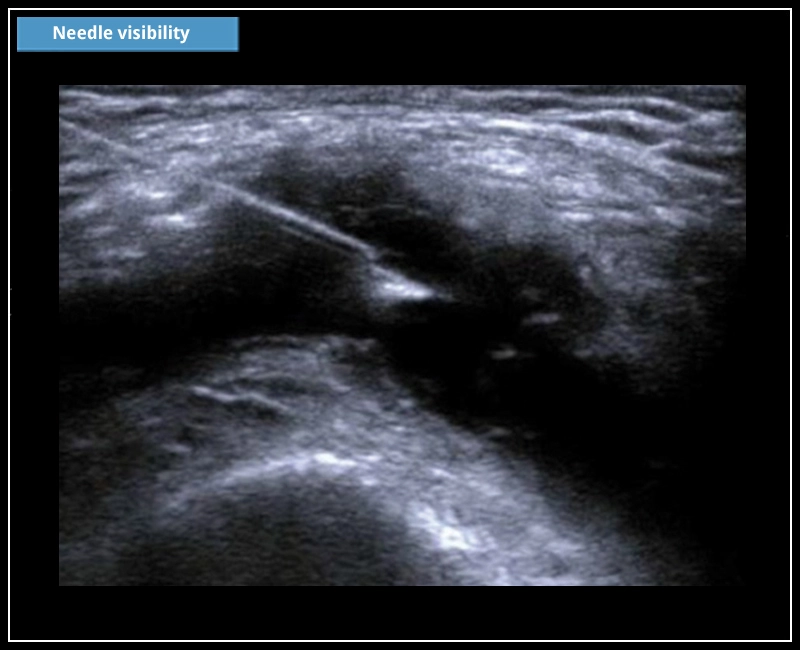

Wählen Sie aus einem großen Sondenangebot. Schallköpfe sind das Herzstück der Ultraschalltechnologie. Das Design, das Material und die Fertigungstechnologie von Schallköpfen bestimmen die Bildqualität eines Ultraschallsystems. Dank der Innovation von Goldstandard-Ultraschallköpfen bieten iQProbes eine Bildgebung nach dem letzten Stand der Technik.